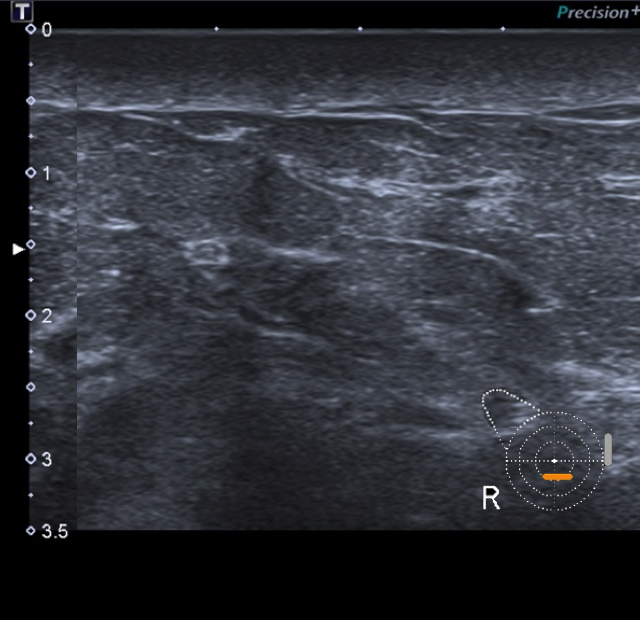

Mujer de 67 años con antecedentes personales de carcinoma ductal infiltrante de mama derecha (pT2 pN1a estadio IIB), tratado con cirugía conservadora + QT + RT + HT hace 6 años.

Actualmente consulta por induración de la mama derecha (MD) con lesiones cutáneas eritemato-violáceas.

1. ¿Cuál sería tu informe radiológico de la mamografía y ecografía y qué recomendarías?

- D. Cambios morfológicos en MD en relación con sus antecedentes, con engrosamiento cutáneo en CCII de MD de nueva aparición (BI RADS 4). Se recomienda biopsia cutánea (punch).